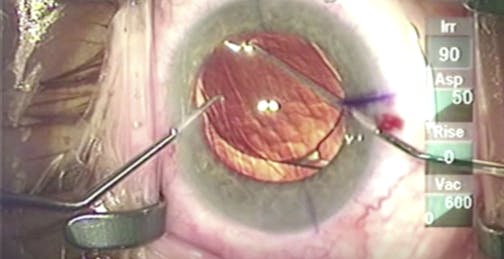

Intumescent Cataract

Lisa Brothers Arbisser, MD